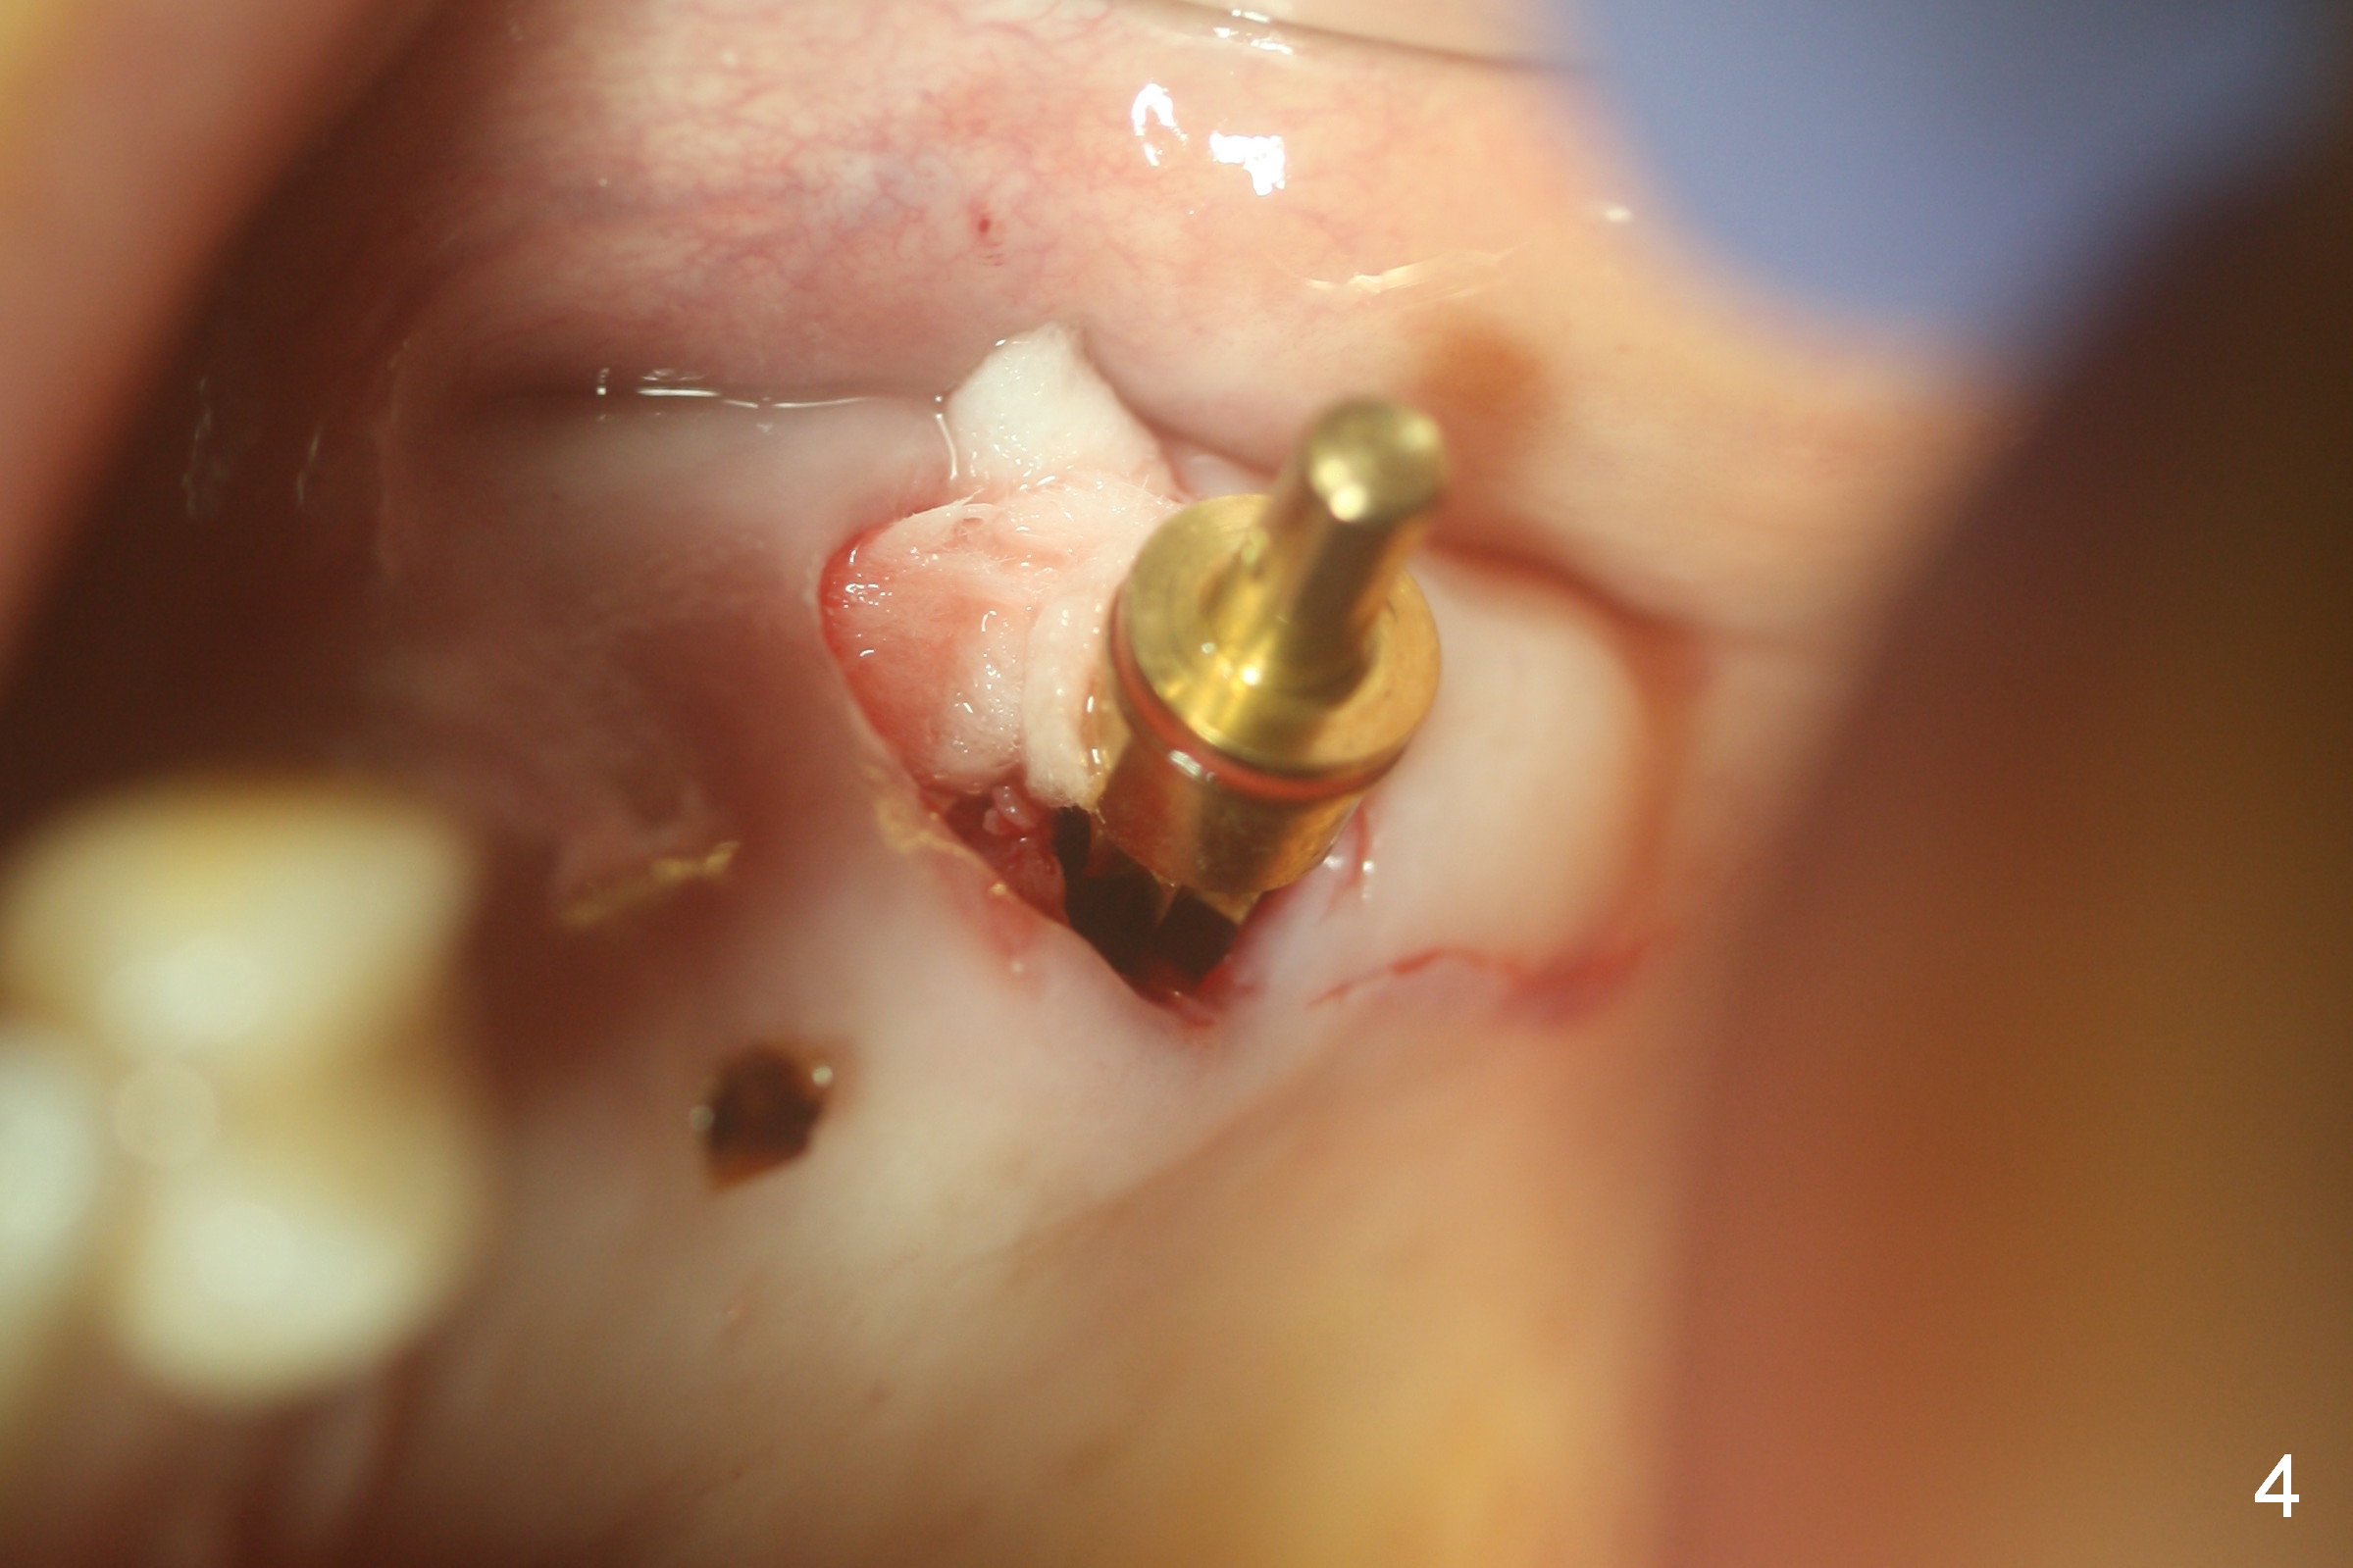

Fig.1,2 show the close relationship of the upper flipper and the residual roots at #15.  Atraumatic extraction using periotomes and surgical sectioning still results in perforation of the mesiobuccal socket (Fig.3 >).  The distobuccal one is shallow, while the septum is small.  It appears that the palatal (Fig.3 P) socket is the most ideal recipient site for the immediate implant and is expanded with Magic Osteotomes until 4.3 mm (Fig.4,5) with the coronal end pushed as buccal as possible.  After placing allograft for sinus lift (Fig.6 >), a 5x11 mm IBS implant is placed with insertion torque ~ 50 Ncm.  A 6x4(3) mm pair abutment is placed, followed by bone graft in the remaining sockets (Fig.6 *) and by Osteogen plug (Fig.7 *).  Finally the socket is sealed by applying acrylic over the abutment (Fig.8).  While the acrylic is setting, the flipper is seated and excess acrylic is removed and pushed away from the flipper (Fig.9).  Advise the patient not to wear the flipper.  If it is being worn, there will be minimal contact between the flipper and the immediate provisional.